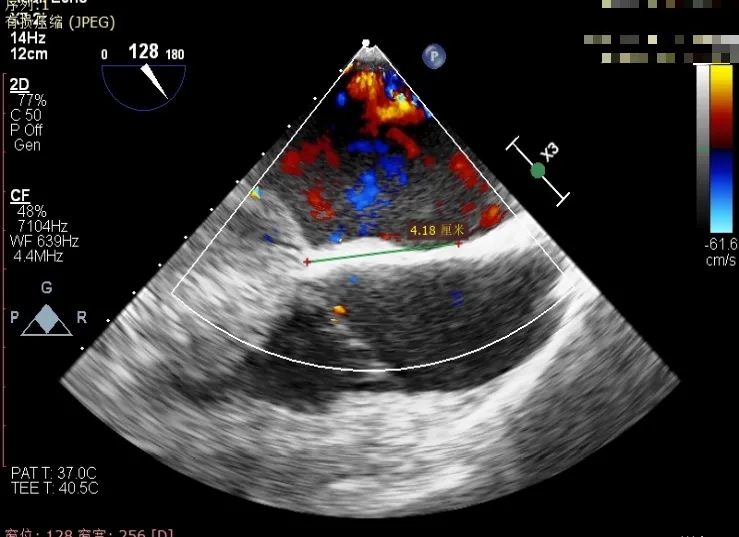

经食道超声精细化测量:肺静脉逆流,房间隔可穿刺高度约4.2cm,Flail宽度约21mm,Flail高度约8mm,Flail Gap约4mm, 3区AML长约23mm、PML长约12mm、2区AML约32.2mm,PML约16mm。

房间隔可穿刺高度约4.2cm

Flail宽度约21mm,Flail高度约8mm

房间隔穿刺高度4.1cm